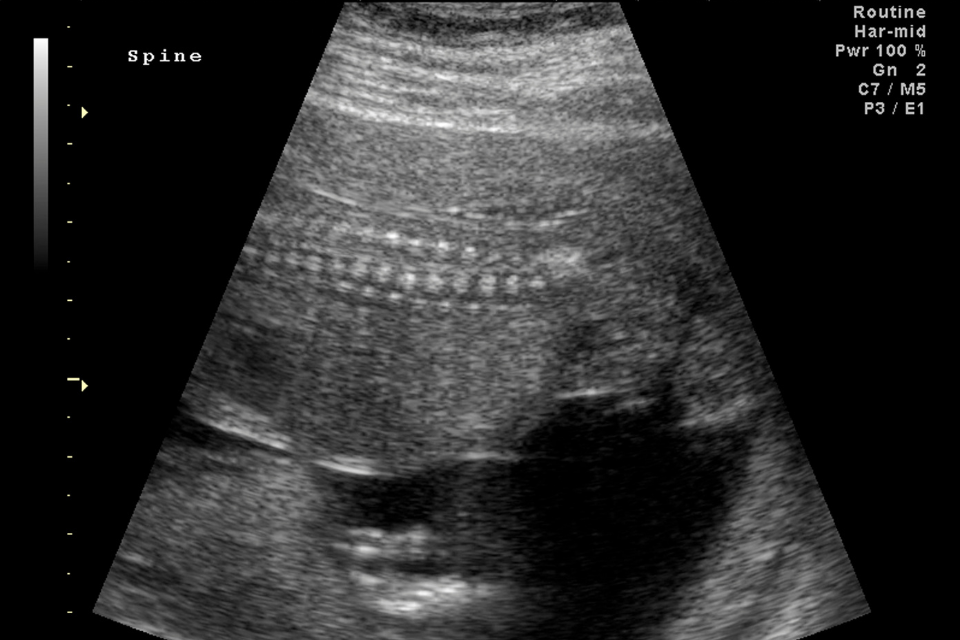

Ved ultralydsscanning kan man danne billeder af både led, sener, muskler, ledbånd, slimsække og i nogle tilfælde også af knogleoverflader.

Skanningen er effektiv til at lokalisere skader i muskler, sener og led -især skulder, albue og hånd samt hofte, knæ og fod/ankel.

Scanningen vil blive foretaget med det nyeste udstyr.